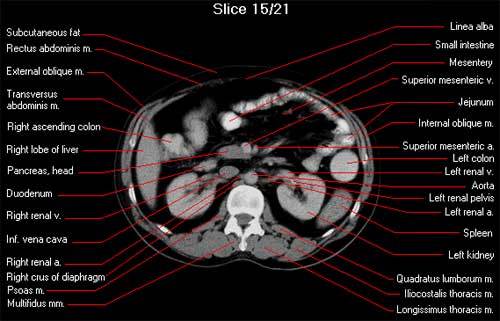

Go over abdo CT structures